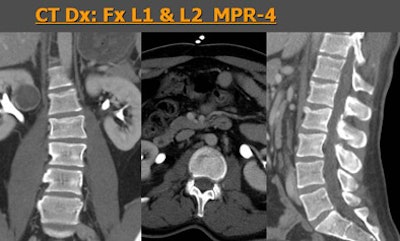

![]() |

| Sixty-four-row MDCT images of a patient who suffered a moving vehicle accident. Axial images (above) show a very subtle line seen by one observer but missed by a second reader. However, MPRs (below) clearly show vertebral fractures at L1 and L2, adding significantly to the value of the scan -- perceived value of MPR was rated 4. |